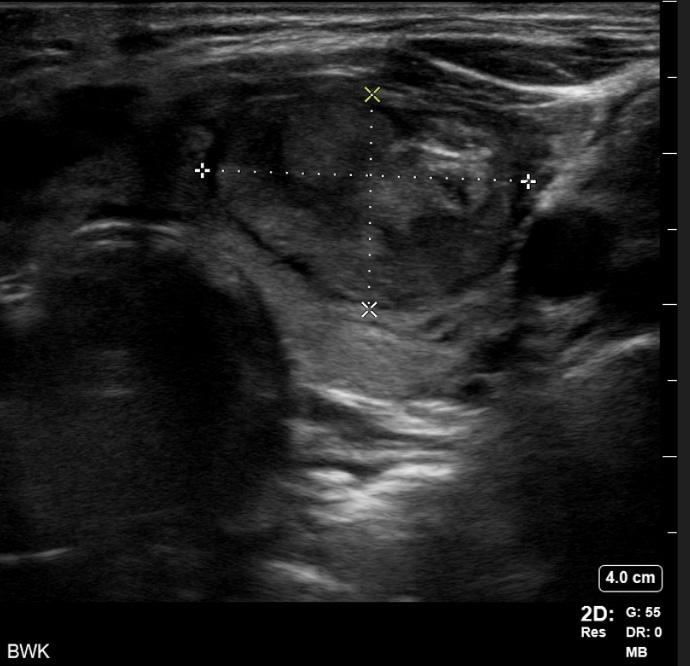

During her physical exam, I noticed the patient had a protuberant thyroid on the left side of her neck, causing cosmetic deformity and easily visible in any neck position. Ultrasound imaging confirmed the patient had multiple

thyroid nodules. She had no overt manifestations of thyrotoxicosis such as tremor, tachycardia, flushing or diaphoresis. She had no evidence of thyroid eye disease or exophthalmos. She was otherwise well appearing with a normal neurological examination.

Thyroid Ultrasound

The right lobe was heterogeneous with parenchymal hypervascularity, measuring 4.9 x 1.5 x 1.1 cm. There were three nodules present, all of them less than a centimeter in size. None of the nodules had highly suspicious features. The isthmus also had no significant nodules and was not thickened.

The left lobe was heterogeneous and measured 5.5 x 2.4 x 2.4 cm, with two notable nodules in her left thyroid lobe. There was a smaller mostly cystic nodule, which measured 2.2 x 2.1 x 2.2 cm. She also had a larger heterogeneous,

hypervascular solid nodule that contained internal microcalcification located in the left middle inferior lobe. This nodule measured 3.0 x 3.1 x 2.3 cm (calculated tumor volume = 11.3 mL).

When comparing the imaging to the nuclear medicine iodine scan, the dominant left solid hypervascular nodule appeared to correspond to the area of increased uptake on the thyroid scan, and clinically this was deemed most certainly the hot or toxic nodule.

Once the perithyroidal block was completed, the RFA electrode (the size equivalent of an 18-gauge needle) was inserted using ultrasound guidance into the known dominant toxic nodule on the left. Utilizing a transisthmic approach and the “moving shot” technique, I sequentially ablated the dominant left-sided nodule. A maximum of 40 watts was used via a 7 mm active tip electrode, with a total ablation time of about 20 minutes.

I monitored each segment of ablated nodule for hyperechoic “bubbling” visible on ultrasound, and for rising impedance from the electrode generator, to assure adequate ablation throughout. During the critical portion of the procedure, I asked the patient to vocalize to assure that no acute voice changes or hoarseness was observed. None were noted and the patient tolerated the procedure well. A bandage was placed over the needle site and the patient was observed for one hour prior to discharge home. Follow-up was arranged for set intervals (one, three, six and 12 months following the ablation) with ultrasound examination of the nodule and thyroid function lab testing.

Just a few months following the procedure, the patient had completely normal thyroid function restored and is doing very well. Her TSH returned to the normal range following the procedure (1.08)

and she reports that her hyperthyroid symptoms resolved. She feels like the nodule is reducing in size with less compression symptoms in her neck, and she has a more normal neck contour. Volumetric ultrasound analysis of her treated nodule at six months shows that her nodule is now less than 3 mL in volume, a 75% decrease in volume from pre-procedure baseline. Further, the procedure did not cause hypothyroidism necessitating thyroid hormone replacement, a known complication of both surgery and radioactive iodine.